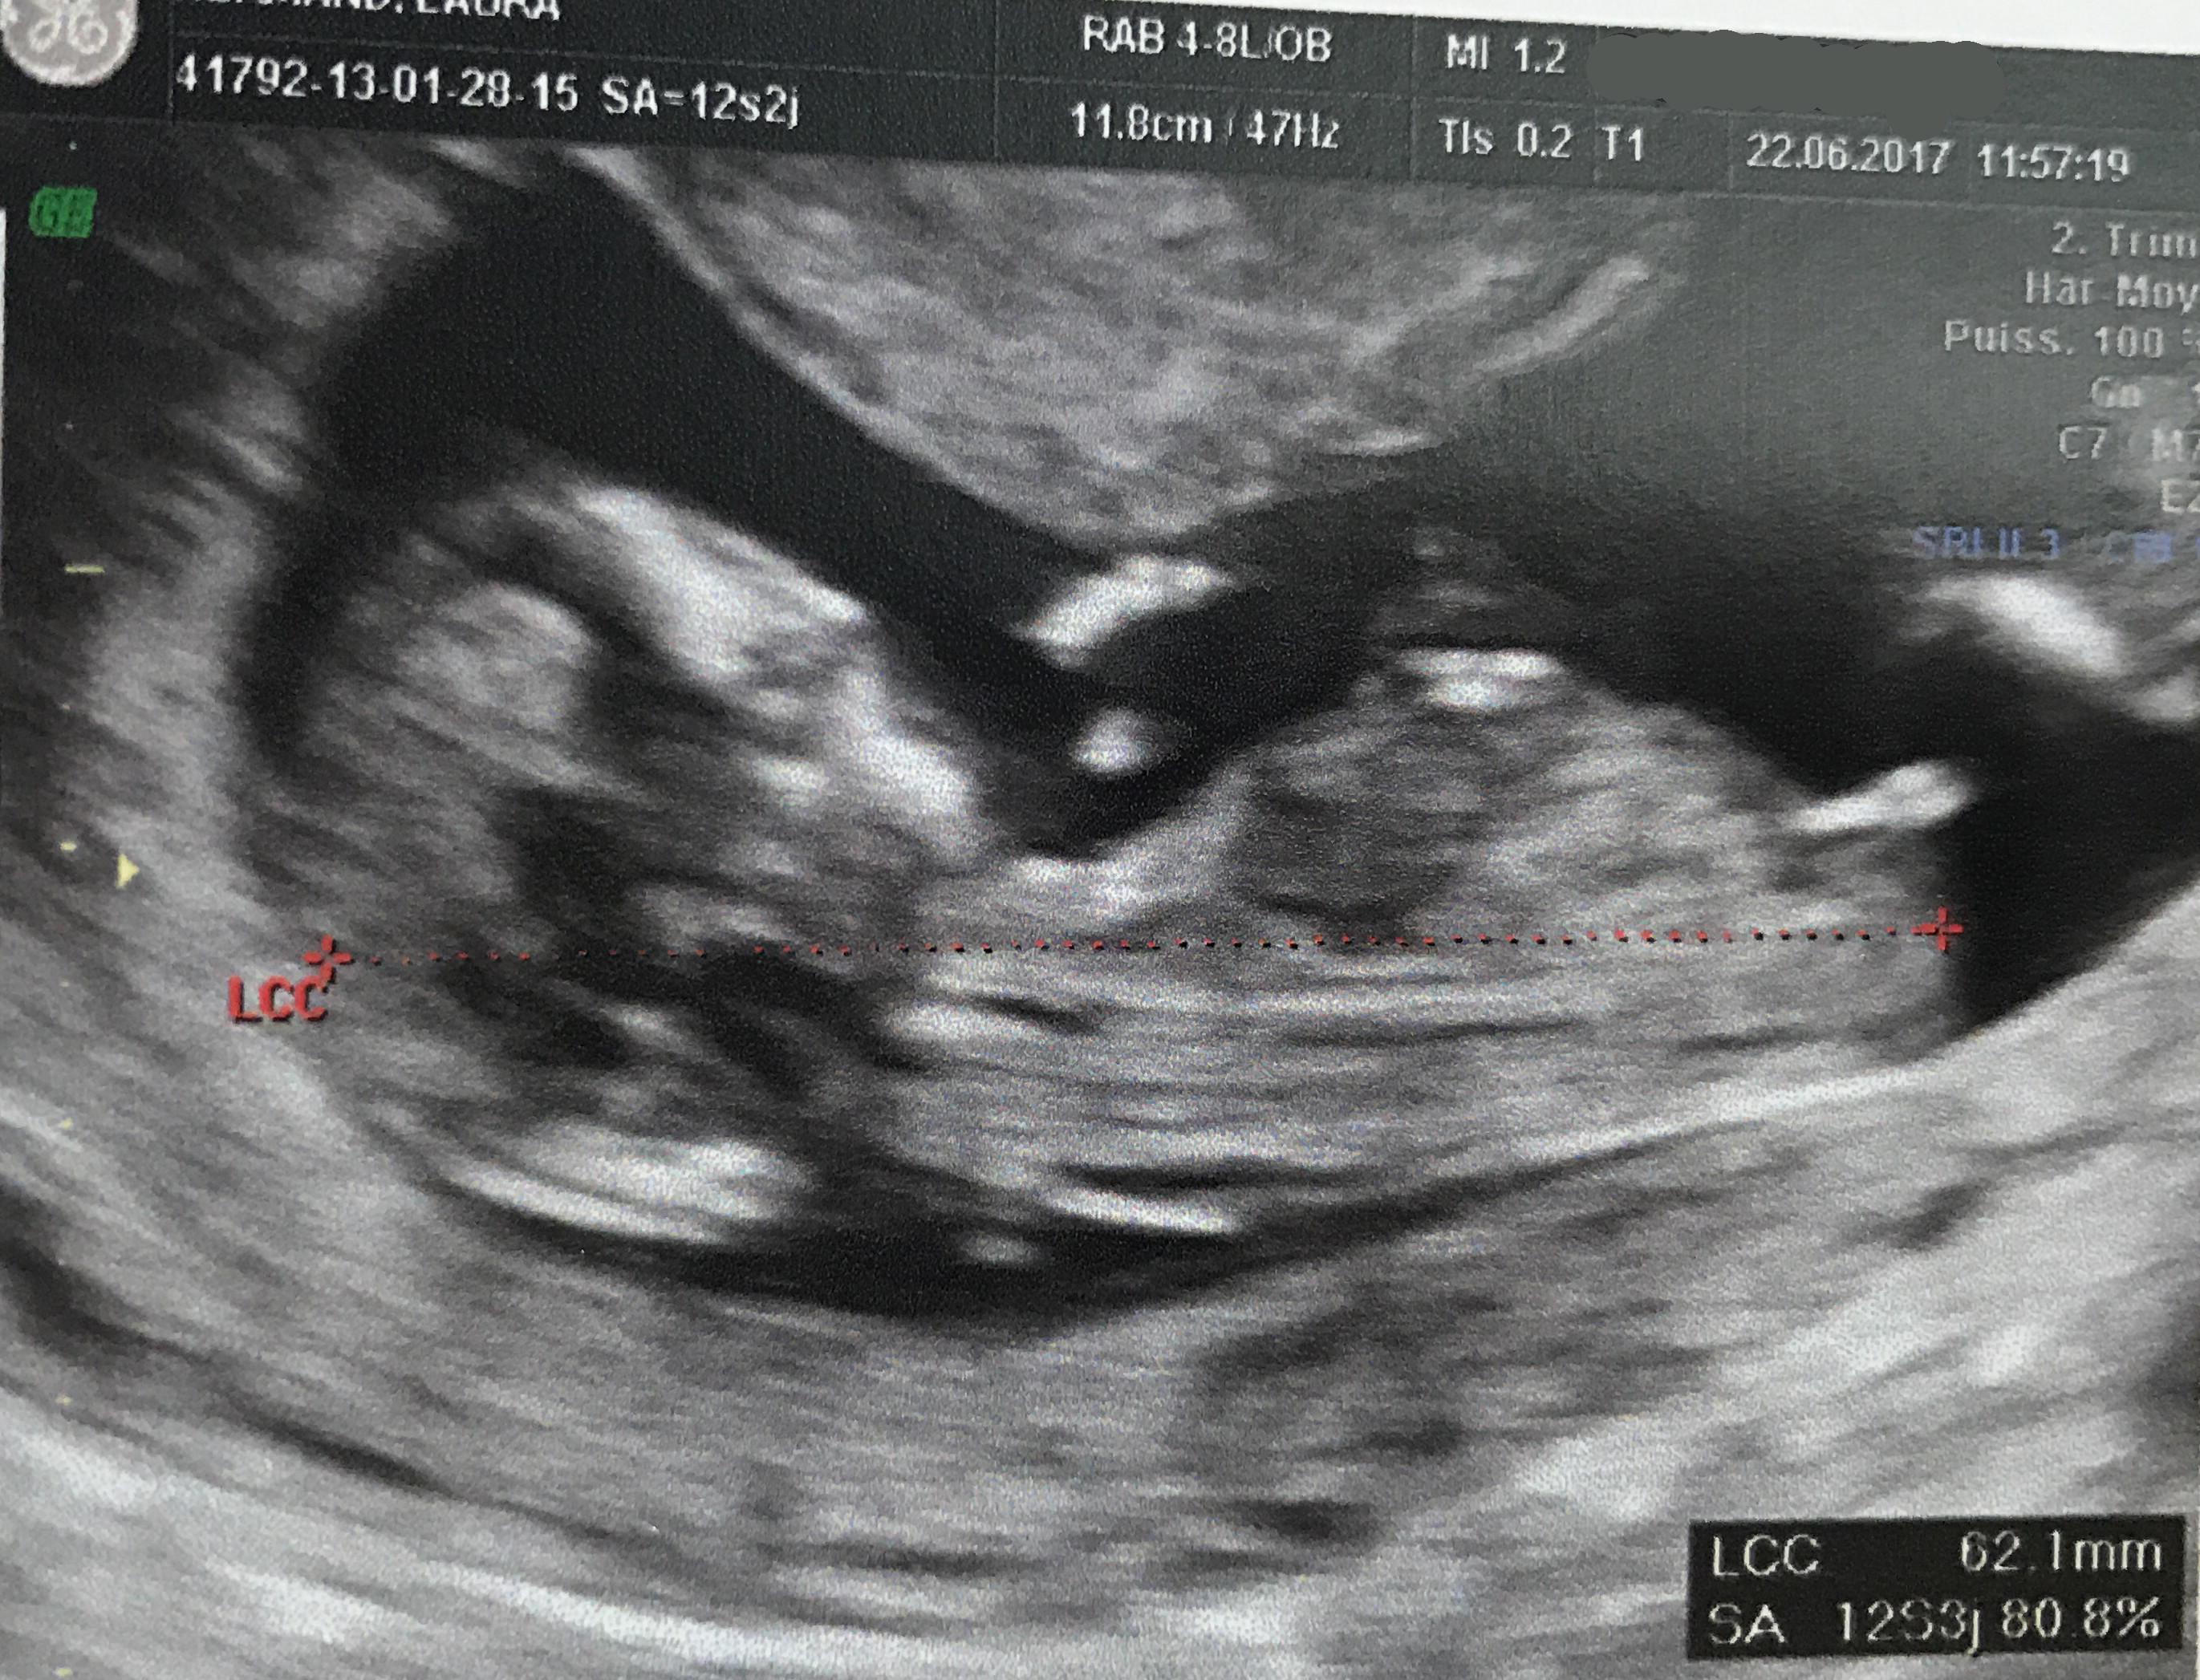

Estil possible de choisir le sexe de bébé?Echo Show 8 (1st Gen, 19 release) HD smart display with Alexa – Unlimited Cloud Photo Storage – Digital Photo Display Charcoal Amazon $ $ 109 99 (238,125)Ainsi dans de bonnes conditions techniques (échographiste entrainé, échographe performant et adapté à l'échographie de grossesse, bon passage des ultrasons à travers la paroi maternelle, bonnes positions du foetus et surout terme de grossesse supérieur à 12,5 SA), le diagnostic du sexe foetal est possible dans plus de 90 % des cas au premier trimestre

Analyser son échographie pour connaître le sexe de bébé Il vous faut donc passer l'échographie T1 (entre 11 et 13 semaines d'aménorrhée) pour avoir des éléments de réponse C'est généralement un grand moment dans votre calendrier de grossesse, émouvant pour les parents, car le fœtus commence à ressembler à un bébéLes envies peuvent également indiquer le sexe du bébé Quand on a envie de manger des produits sucrés, comme du chocolat, des biscuits, ou des bonbons, c'est une fille à l'intérieur du ventre Si l'on opte plutôt pour des frites ou n'importe quelle autre forme d'apéritif salé, c'est un garçonLa 1ère chose qu'elle nous a demandé, c'était de savoir si on voulait connaitre le sexe de cookie En France, il avait fallu qu'on demande au gynéco (un vieux monsieur un peu bourru) à la fin de l'examen pour savoir pour Mlle E lors de cette écho

Échographies Le moyen le plus fiable de connaître le sexe du bébé est l'échographie"La première échographie se déroule au cours du troisième mois de grossesse entre la 11e et la 13e semaines d'aménorrhéeDans certains cas, le sexe du bébé peutêtre annoncé lors de ce premier examen", explique le Dr Philippe Mironneau, gynécologue etCe matin, nous avons fait notre deuxième échographie Ce matin, après avoir un peu stressé parce que la sagefemme ne disait rien en regardant ce petit cœur battre, elle nous a rassuré en nous disant que tout allait bien pour ce beau bébé de 500 g, qui avait bien poussé Ce matin, nous avons appris qu'une petite fille viendraitRevelation du sexe de bebe , on attend c'est le grand jour, on connait enfin qui se cache dans mon ventreNous sommes des futurs parents comblé♡ Abonne to